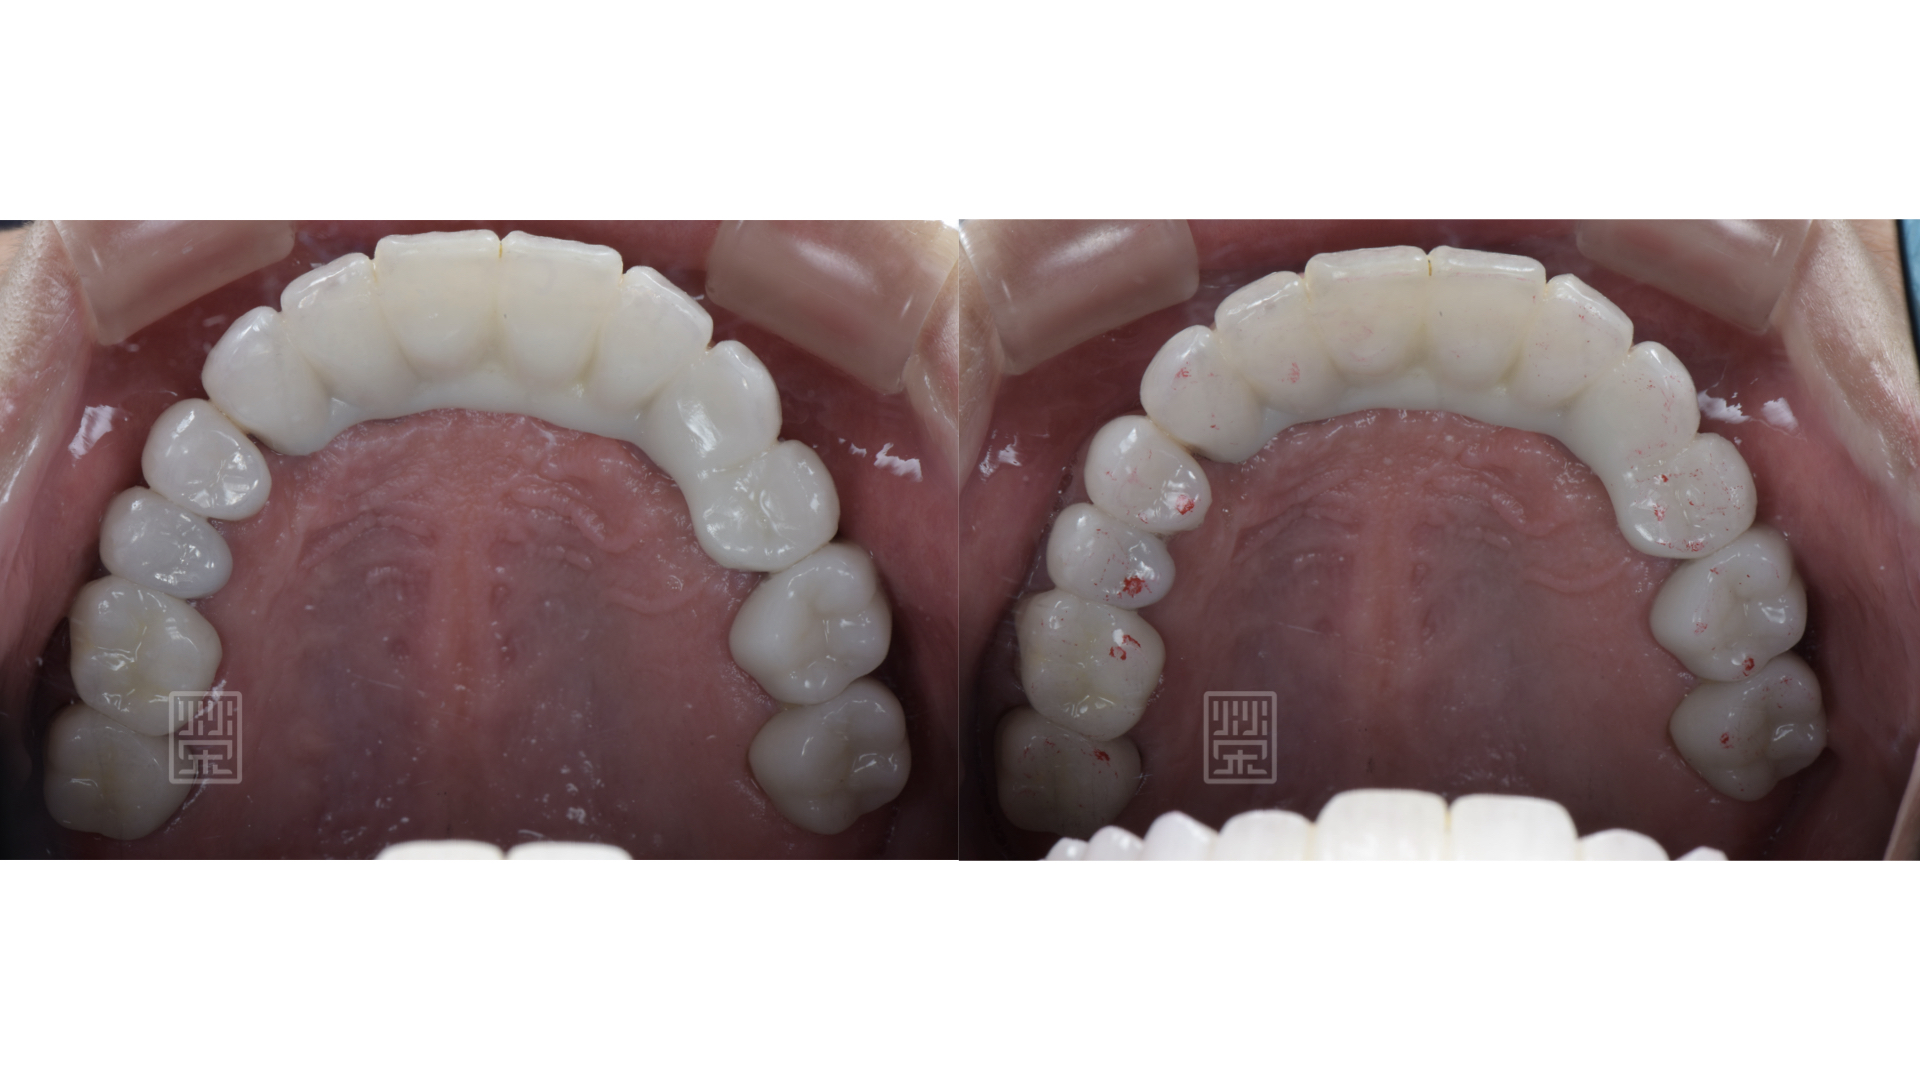

適當的咬合分配

藉由臨時假牙、矯正、更新臨時假牙,讓型態、長度、唇形充分瞭解與溝通